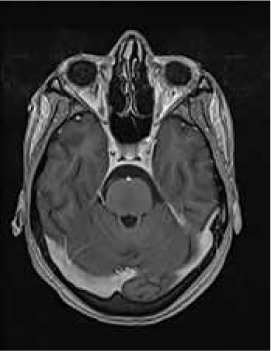

Magnetic resonance imaging (MRI) of the brain showed symmetrically increased T2-weighted and fluid-attenuated inversion recovery signal in the central pons (Figure 1) and in the striatum of the basal ganglia (Figure 2), with no contrast enhancement seen on corresponding T1-weighted postgadolinium images (Figures 3 and 4). Spinal MRI (Figure 5) demonstrated high signal on T2-weighted images from the area postrema in the medulla extending caudally to the T9 thoracic segment, with marked cord swelling and mild enhancement on T1-weighted postcontrast studies (Figure 6), in keeping with a longitudinally extensive inflammatory myelitis.

Magnetic resonance image of brain shows bilateral symmetrical high signal in caudate and lentiform nuclei on axial fluid-attenuated inversion recovery sequences

Postcontrast magnetic resonance image of brain show nonenhancing changes in basal ganglia

The clinical and radiologic features supported the diagnosis of NMO. However, the symmetrical pontine and basal ganglia high signal without contrast enhancement were considered to be strongly suggestive of concomitant ODS (pontine and extrapontine myelinolysis).

Neuromyelitis optica may lead to hyponatremia via at least two mechanisms. Area postrema involvement frequently causes intractable vomiting, and this may result in a low serum sodium level. Moreover, the syndrome of inappropriate antidiuretic hormone may develop in patients with NMO and hypothalamic lesions. In the present patient, the lowest recorded sodium level was 132 mmol/L. However, MRI demonstrated features of both central pontine and extrapontine myelinolysis, which, when occurring together, are considered virtually pathognomonic of ODS.4 Typical features include the symmetrical nature of the changes, the involvement of areas typically affected in ODS (pons, basal ganglia), and the sparing of peripheral pontine fibers. However, it remains a possibility that these radiologic changes were due to NMO primarily rather than osmotic demyelination. In a recent review, Kim et al.5 expanded on the range of MRI abnormalities consistent with NMO and NMO spectrum disorders. Gray matter demyelination of the thalamus and bilateral involvement of the corticospinal tracts have been described, although published examples are not as strikingly symmetrical as in this case and do not show the combination of central pontine demyelination with symmetrical striatal involvement.5 To our knowledge, these typical ODS changes in the context of NMO have been described in only one other case, in the Japanese literature.6